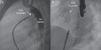

Para el cierre percutáneo del PDA y de la CIA se eligieron los dispositivos Occlutech PDA OccluderTM 3.5/5 (Occlutech International AB, Helsingborg, Suecia) y Figulla Flex II ASD OccluderTM 16,5mm (FFO, Occlutech GmbH, Jena, Alemania) respectivamente, los cuales se implantaron sin complicaciones (fig. 2).

(a) Angiografía en proyección oblicua anterior-derecha que muestra el dispositivo Occlutech PDA Occludder (flecha). La inyección de contraste desde la aorta descendente evidencia la ausencia de shunt residual a través del ductus arterioso persistente. AO DESC: aorta descendente.

(b) Fluoroscopia antero-posterior que ilustra el dispositivo de cierre de CIA, Figulla ASD Occluder (flecha) tras ser liberado.